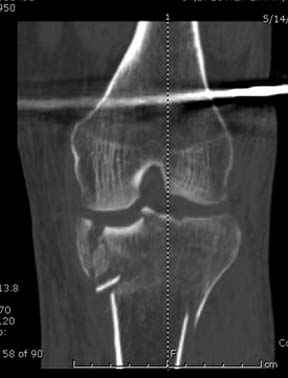

Отдельные переломы тибиал плато и перелом проксимальной трети большеберцовой кости отличаются от переломов тибиал плато с вовлечением диафиза. Здесь перелом тибиал плато типа Schatzker VI, полученный в результате высокоэнергетической травмы. Перелом метафиза образовал отрыв суставной поверхности от диафиза с вовлечением медиального и латерального мыщелков. Двухмыщелковые переломы из-за укрочения опасны развитием компартаментального синдрома, повреждением латерального мениска и связок.

Одна из проблем фиксации тибиал плато - это предупреждение мягкотканых осложнений, и это достигается проведением поэтапной фиксации. Такая тактика - первым этапом дистракция любым наружным фиксатором, а затем по готовности кожных покровов и после спадения отека операция. Операция в ранние сроки и без адекватной готовности кожных покровов лимитирует ваши действия опасностью осложнении, но без адекватного доступа фиксация получается ущербная. Для предупреждения осложнений лучше подождать и в зависимости от серьезности травмы можно ожидать иногда от 1 до 2 недель.

Имеющаяся импрессия не потребовала пластики - достаточным оказалось поднять отломок

Если там действительная импрессия, пустое место без структуральных заполнителей, кость или синтетические материалы, не восстановится, а образуется коллапс, и ось конечности поведет после нагрузки. Кроме того там возможно "болт стяжка"?, в медиальной стороне выступает за кортекс, можно было укоротить! Потом создается впечатление, что не соответствуют мыщелки большеберцовой и бедренной костей? Покажите снимок.